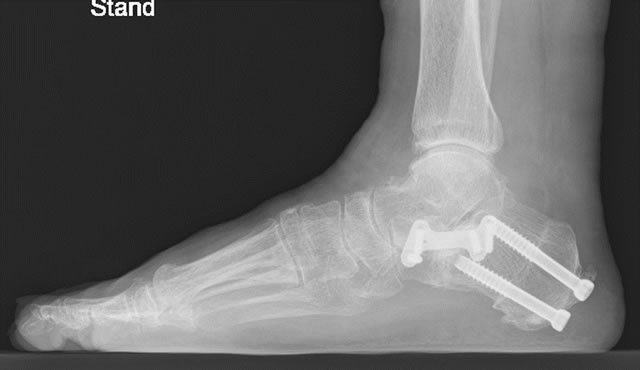

4.扁平足に対する変形矯正術

術前

術後

縦アーチの改善

術後1カ月、ギプス固定で部分荷重歩行開始

術後2カ月、ギプスから着脱可能な装具(サポーター)に変更

術後4カ月、骨癒合を確認し装具終了